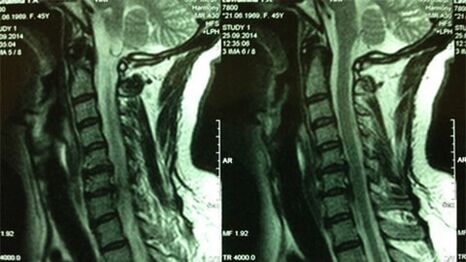

- Servik idorasi bo'limining x----kari Jarayonning boshlang'ich bosqichida, bachadon bo'yni boshqarmasi ma'lumotlari ko'proq ma'lumotga ega bo'ladi - bu qattiq va yumshoq to'qimalarni vizualizatsiya qilishni ta'minlaydi - tomirlar, deformatsiyalar, tomirlar va qon tomirlariga zarar etkazishi mumkin; ligamentlar, mushaklar, suyak to'qimalarining holatini baholaydi;